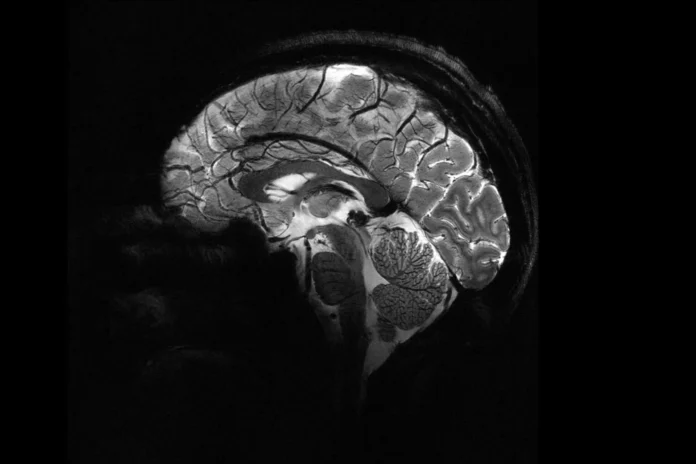

Selon le physicien Alexandre Vignon, une précision inégalée a été atteinte, avec un champ magnétique créé par l’appareil atteignant 11,7 teslas, ce qui lui permet d’effectuer des scans dix fois plus précis que les appareils d’imagerie par résonance magnétique classiques dans les hôpitaux.

Grâce à cet appareil, les chercheurs ont pu observer de petits vaisseaux sanguins alimentant le cortex cérébral, ainsi que des détails du cervelet qui n’étaient pas visibles auparavant.